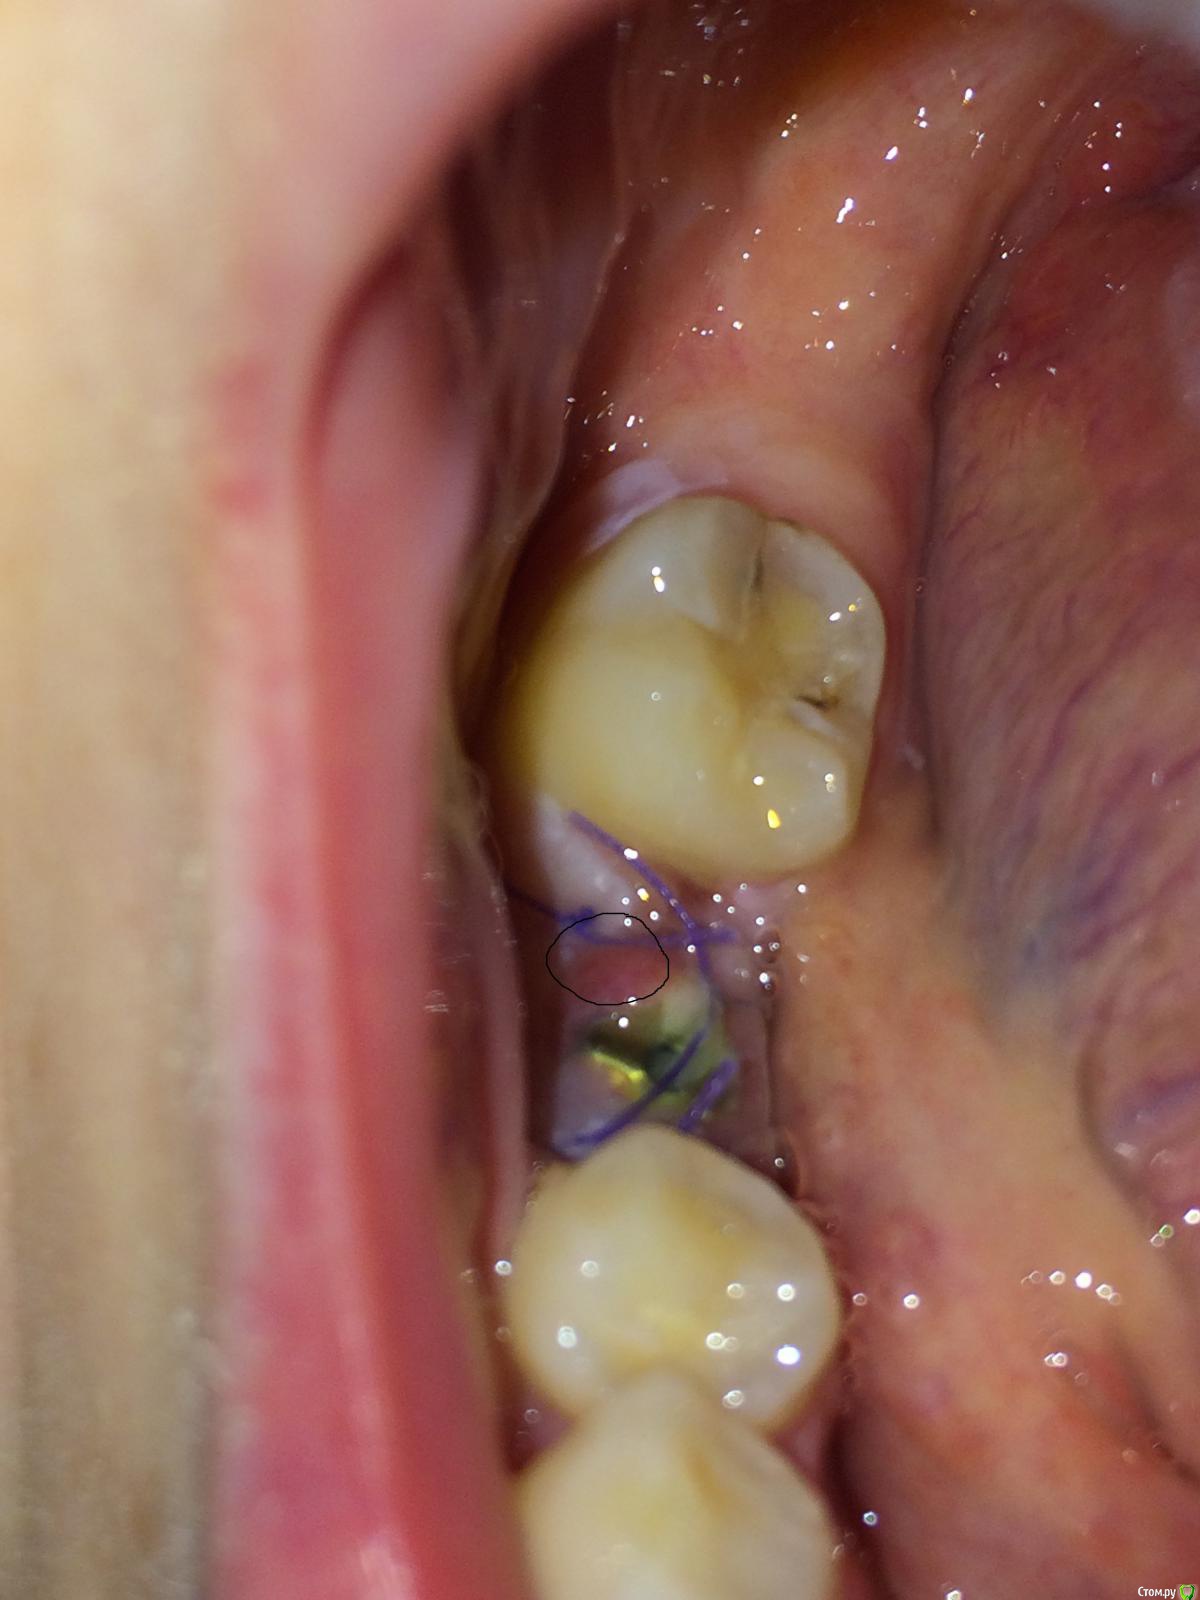

flyfli Опубликовано 20 октября, 2017 Поделиться Опубликовано 20 октября, 2017 (изменено) Уважаемые доктора,помогите ,пожалуйста, очень переживаю,сегодня 5 ый день после имплантации и возле формирователя немного красновато и припухло с одной стороны, боли нет,но очень страшно,все ли впорядке как вы думаете? Такое может быть покраснение нормой? Изменено 20 октября, 2017 пользователем flyfli Ссылка на комментарий

flyfli Опубликовано 20 октября, 2017 Автор Поделиться Опубликовано 20 октября, 2017 там формирователь, вот попробовала поближе там обвела кружком подозрительное место Ссылка на комментарий

red_butler Опубликовано 20 октября, 2017 Поделиться Опубликовано 20 октября, 2017 там формирователь, вот попробовала поближе там обвела кружком подозрительное местотогда ничего страшного, антисептическая обработка и ждать Ссылка на комментарий